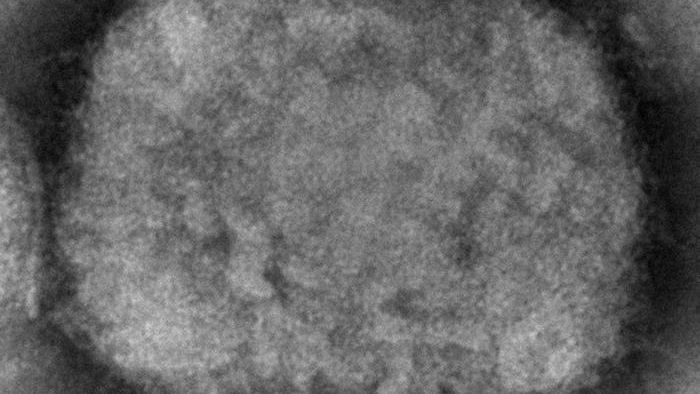

The disease, formerly known as monkeypox, is caused by a virus similar to the one that causes smallpox.